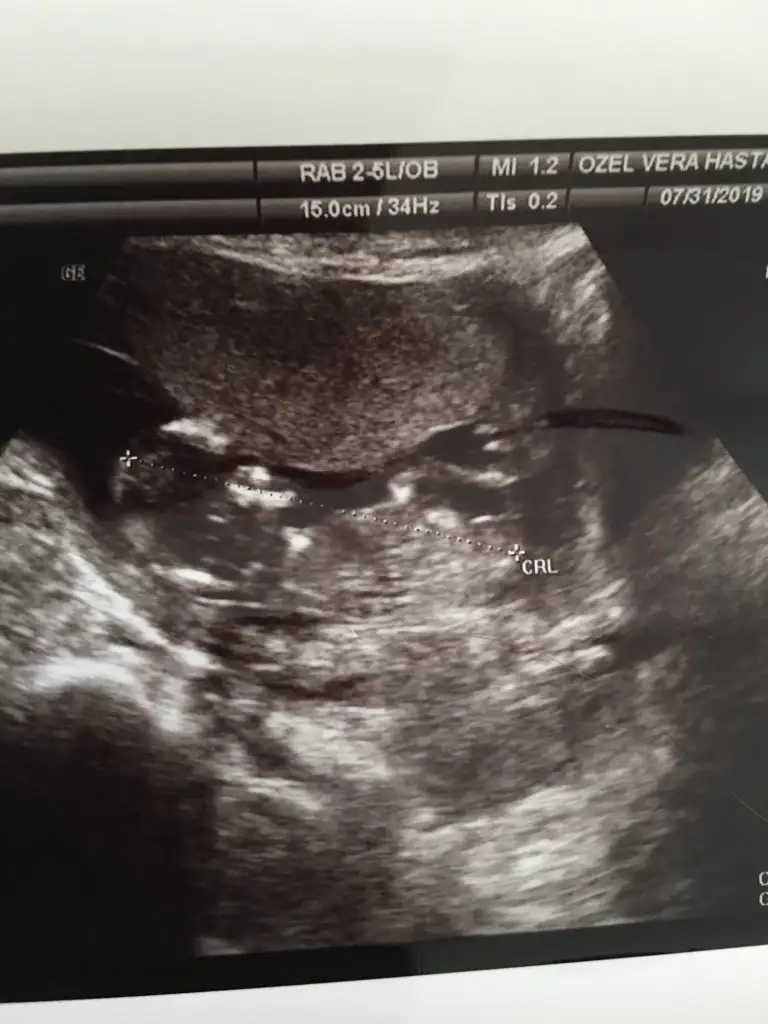

Benim doktor tahmin yapmaya çalıştı canım önce yüzde 70 erkek dedi poposu hafif kalkikti sonra pozisyon değiştirince aaa bu erkek değil kız dedi aynen ya bak şimdide kız dedi bı beş dk döndükçe baktık bu sefer kız gibiydi neyse dedi biz bı tahmin yapmayalım açı değişiyor kipirdadikca dedi ama erkek olması içinde çok dik degildi ucundan 30 dereceydi en iyisi on gün sonra gelince kesin söyleyelim dış genital organı olussun bekleyelim dedi.